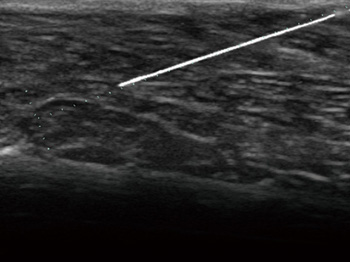

- Функция Smart Navigation: отслеживание пути иглы с помощью цвета при проведении биопсии

- Технология BEAM для автоматического отображения пункционной иглы в реальном времени

Опция улучшения визуализации иглы. С помощью этой функции вы сможете добиться улучшенного изображения при вводе иглы во время проведения биопсии и целого ряда подобных исследований. Нужная вам область будет выделена автоматически при инвазивном вмешательс